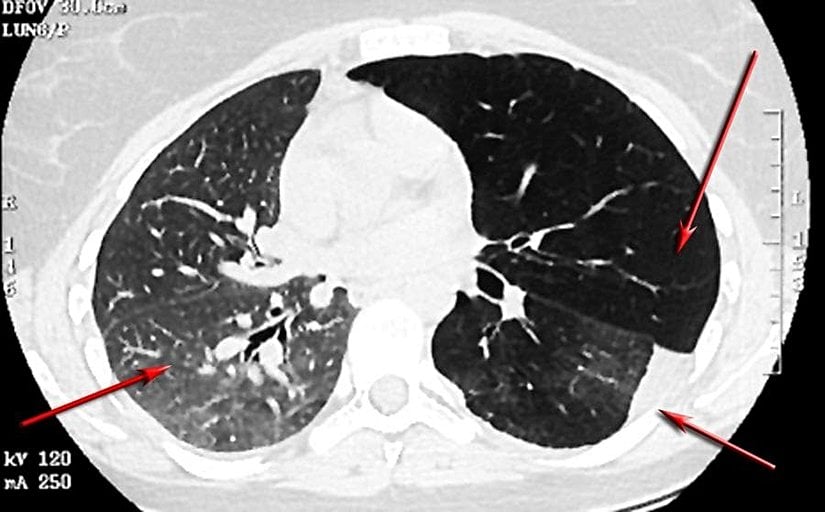

Çeşitli hava yolu tümörlerinin astıma benzer semptomlarla kendini gösterdiği rapor edilmiştir. Bu tümörler, aşağıdaki resimlerde gösterildiği gibi endobronşiyal karsinoid ve mukoepidermoid tümörleri içerir. Bir vakada, sol akciğerinde hiperlüsensi olan 14 yaşındaki bir erkek çocuğunun nihayetinde sol ana bronşta bronşiyal karsinoid olduğu bulundu.[119]

Diğer trakeal lezyonlar arasında bronkosentrik granülomatozis, subglottik stenoz, subglottik ağ, trakeal hamartom, bronkojenik kistler, leiomyoma ve trakeobronkopatia osteoplastika yer alabilir. Tüm bu trakeal lezyon tipleri astıma benzer semptomlarla rapor edilmiştir.

Diffüz Panbronşiolit

Diffüz panbronşiolit Japonya ve Uzak Doğu'da yaygındır ve hırıltılı solunum, öksürük, egzersiz sırasında nefes darlığı ve sinüzit ile bronşiyal astımı taklit edebilir.[122] BT bulguları arasında, bazen astımda gözlenen multifokal bronşiolar impaksiyondan genellikle daha bol olan sentrilobüler nodüller ve lineer işaretler bulunur.